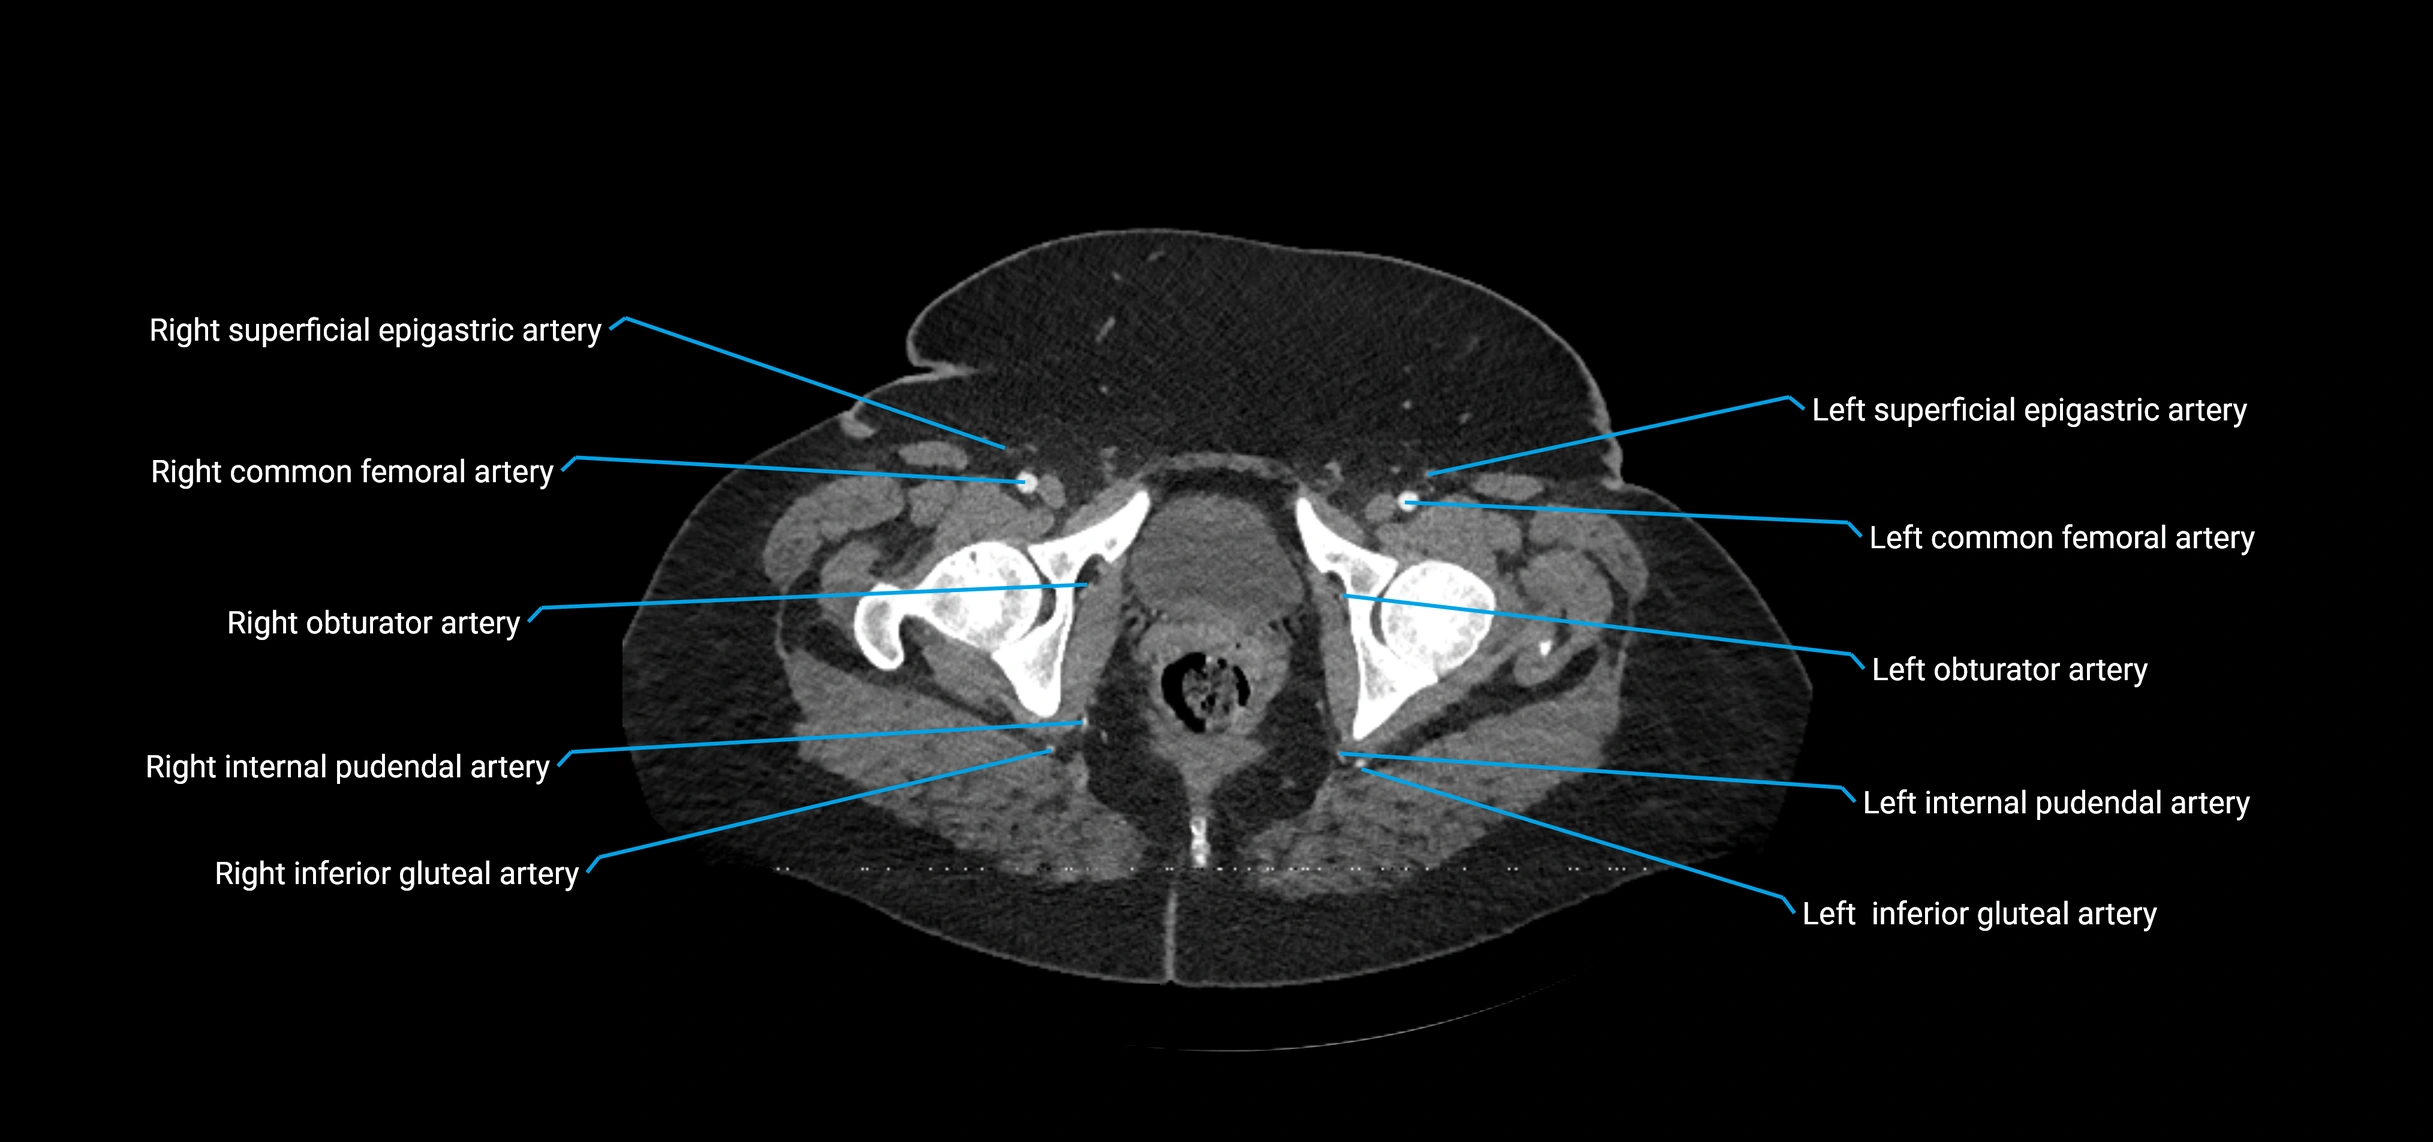

Contrast-enhanced CT (CTA):

• Gold standard for abdominal aortic imaging

• Provides excellent detail of lumen, wall, aneurysm, thrombus, and branch vessels

• Multiplanar and 3D reconstructions help in aneurysm measurement, stent graft planning, and dissection evaluation

• Detects acute rupture, traumatic injury, or occlusion with high sensitivity